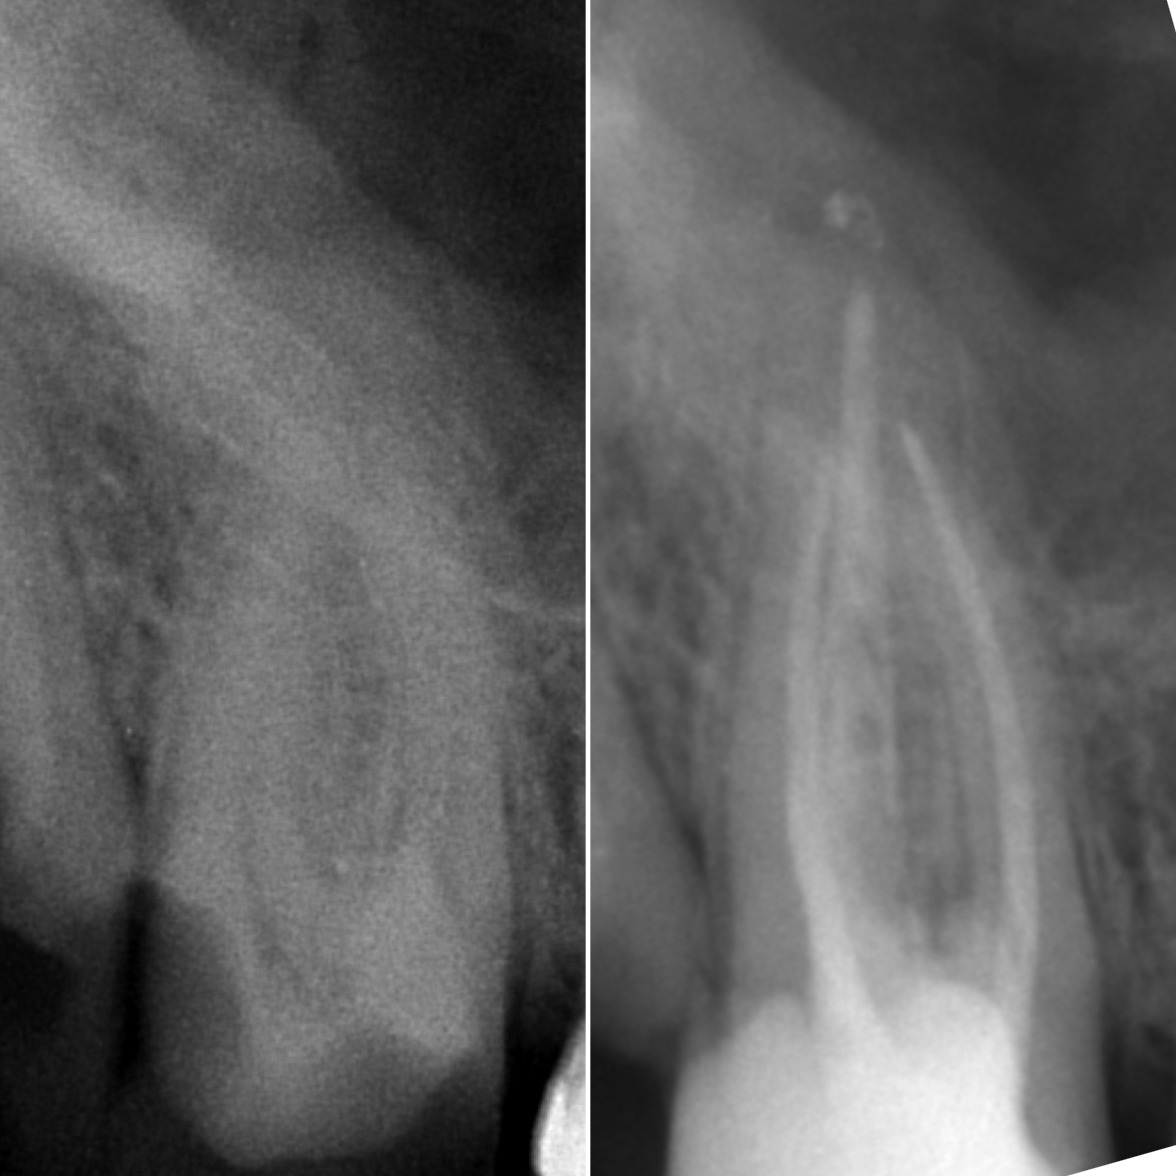

• Диагностика и лечение кариеса и его осложнений (пульпиты, периодонтиты)

• Эндодонтическое лечение корневых каналов с использованием стоматологического микроскопа